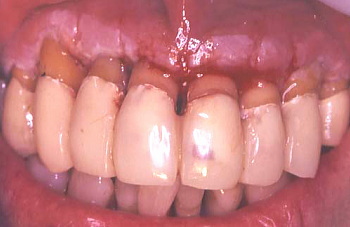

治療前と治療後の口腔内を比較

初診時の口腔内の状態

最終治療後の状態